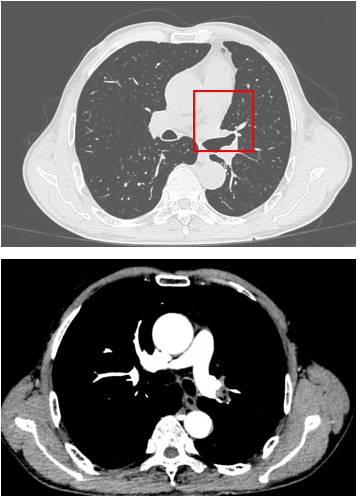

PET-CT(2023年9月):右下肺叶发现6.9×6.7×6.6cm的FDG高摄取肿块,伴右侧第7、8肋骨侵犯可疑,右肺门淋巴结肿大,双肺上叶多发结节,考虑腺癌谱系疾病。

CT及PET-CT随访(2023年11月、2024年1月):评估新辅助治疗效果,右下肺叶肿块缩小,右肺门淋巴结代谢活性消失,右肺上叶结节稳定但代谢活性降低,左肺上叶及双侧磨玻璃样病变稳定。